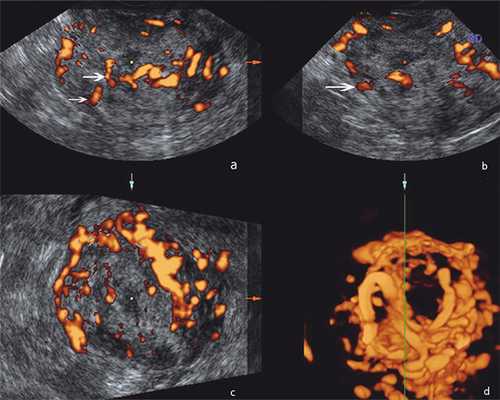

Сонографическая картина образования характеризовалась бугристым контуром, в структуре были анэхогенные аваскулярные участки, кровоток определялся хаотично по всех поверхности, в т.ч. в центральных отделах узла, показатель индекса резистентности (IR) был в пределах 0,5-0,45 мм/сек (рис. 1), на основании чего был предложен диагноз саркома матки.

Рисунок 1. Эхограммы с энергетической допплерографией органов малого таза у больной Х.: а, б, в) образование миометрия с бугристым нечетким контуром, неоднородной структуры за счет гипоэхогенных участков в структуре, хаотичным кровотоком по всей поверхности (стрелки), показатель индекса резистентности (IR) 0,5-0,45 мм/сек; г) 3D-реконструкция, извитой ход сосудов, васкуляризация по типу клубка.